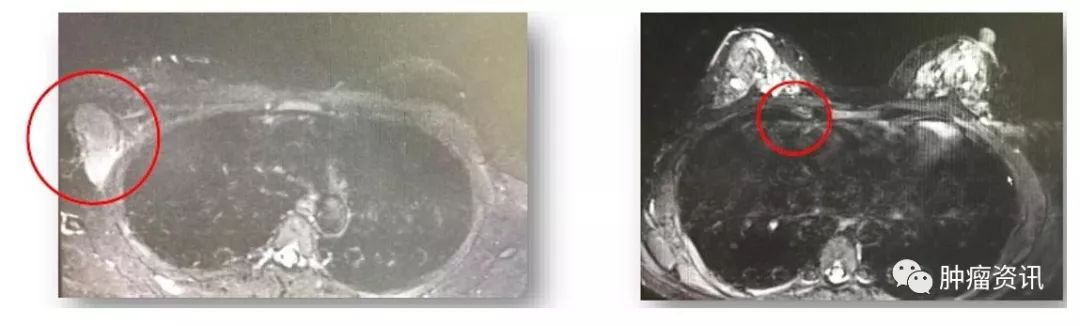

实验室检查:血肿瘤标记物:CA153 32.4U/ml,CA125 46.43 U/ml,CEA 5.92 ng/ml。乳腺MRI示(图1):右腋窝、右锁骨上肿大淋巴结,最大为38mm×38mm,强化明显,符合转移。右胸廓内动脉旁小淋巴结,9mm×8mm,强化明显,不除外转移。双乳可见直径为3~6mm多发小结节,等T1稍高T2信号,考虑为增生结节,余未见明显。颅脑MRI未见明显异常。PET-CT示(图2):右锁骨上、右腋窝多个肿大淋巴结,最大约为25mm×32mm,SUVmax为18,符合转移瘤,余未见明显异常。

图1 患者入院乳腺MRI